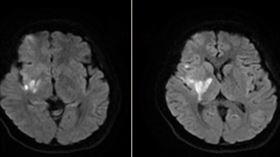

爆炸性頭痛別忍 年輕人中風主因是它

27歲的張小姐,某天上班時突然感受到一陣突如其來的爆...